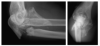

The eponym Monteggia fracture dislocation originally referred to a fracture of the shaft of the ulna accompanied by anterior dislocation of the radial head that was described by Giovanni Battista Monteggia of Italy in 1814. Subsequently, a further classification system based on the direction of the radial head dislocation and associated fractures of the radius and ulna was proposed by Jose Luis Bado of Uruguay in 1958. This article investigates the evolution of treatment, classification, and outcomes of the Monteggia injury and sheds light on the lives and contributions of Monteggia and Bado.